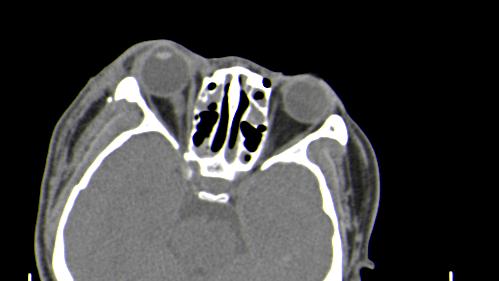

以下是引用皎皎白驹在2006-11-29 8:48:00的发言:[br]影像表现:双侧筛窦和上颌窦、鼻腔内均密度增高,右侧视神经增粗、弯曲,左筛窦顶部筛板及右侧纸板近视神经孔区可见骨折线。[br]结合临床表现考虑:右侧筛窦纸板近视神经孔区骨折致右侧视神经损伤。最好做个眼眶冠状扫描,更明确右侧视神经管是否狭窄。

以下是引用w_jianhua在2006-11-29 10:07:00的发言:[br]影像表现:双侧筛窦和上颌窦、鼻腔内均密度增高,右侧视神经增粗、弯曲,左筛窦顶部筛板及右侧纸板近视神经孔区可见骨折线。[br]结合临床表现考虑:右侧筛窦纸板近视神经孔区骨折致右侧视神经损伤。最好做个眼眶冠状扫描,更明确右侧视神经管是否狭窄。 [br] [br]支持[br]

以下是引用守望可可西里在2006-11-29 9:46:00的发言:[br][quote]以下是引用皎皎白驹在2006-11-29 8:48:00的发言:[br]影像表现:双侧筛窦和上颌窦、鼻腔内均密度增高,右侧视神经增粗、弯曲,左筛窦顶部筛板及右侧纸板近视神经孔区可见骨折线。[br]结合临床表现考虑:右侧筛窦纸板近视神经孔区骨折致右侧视神经损伤。最好做个眼眶冠状扫描,更明确右侧视神经管是否狭窄。